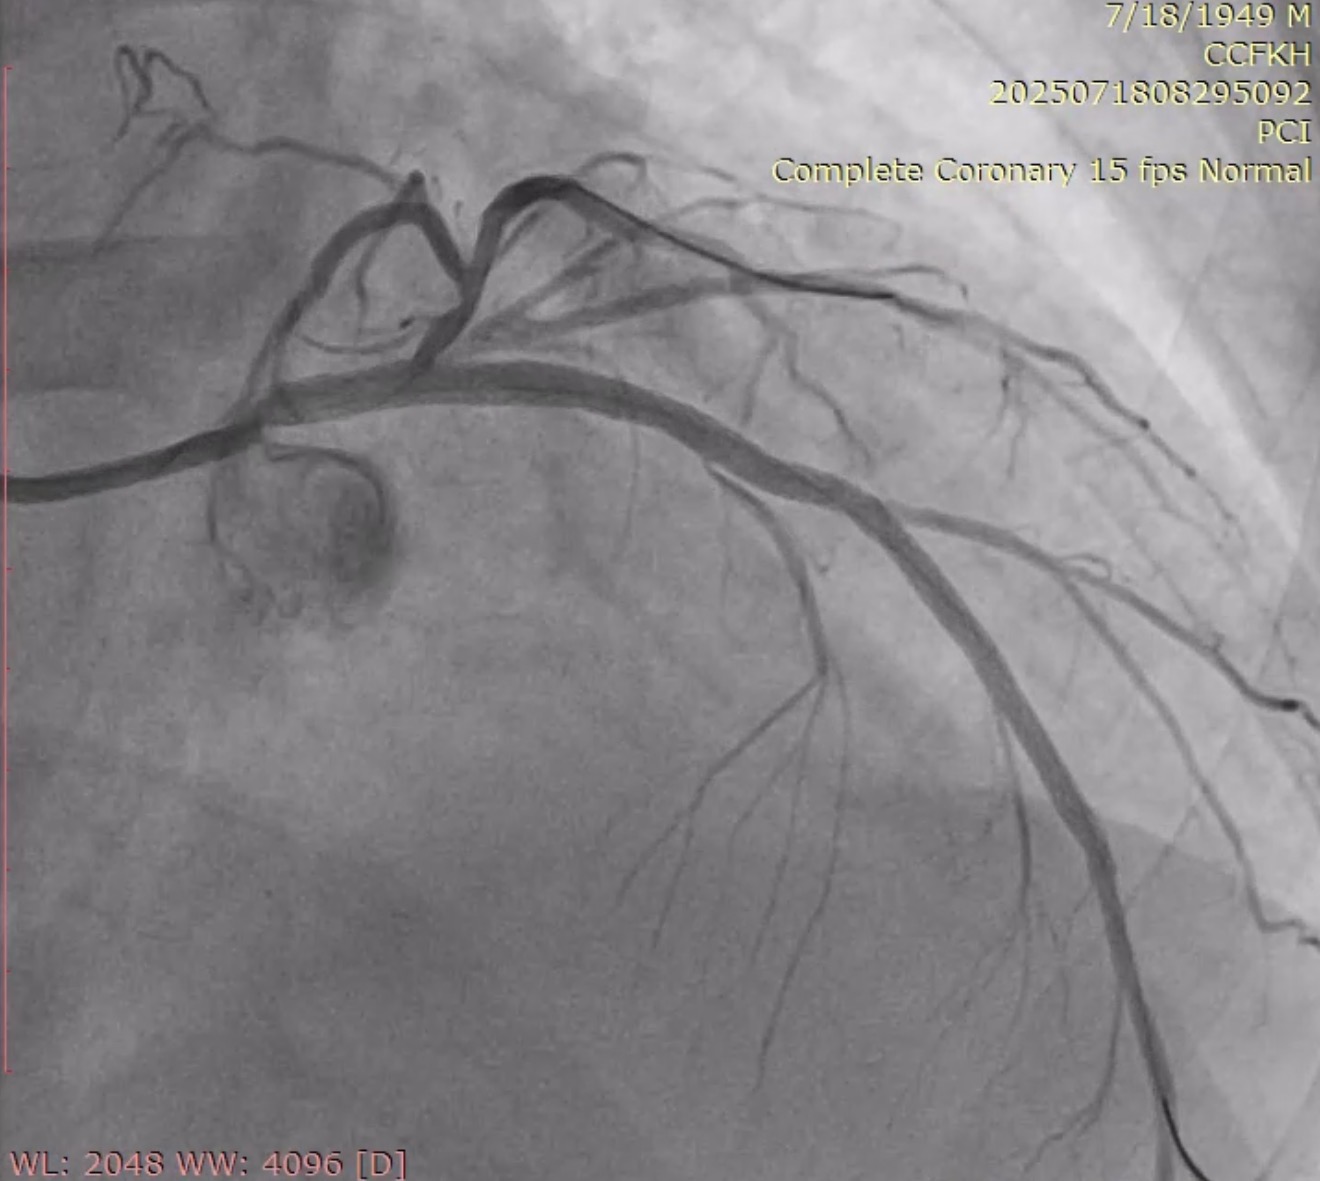

Urgent coronary angiography was performed by using right radial artery approach, which surprisingly showed left main coronary artery (LMCA) total occlusion with TIMI 0 flow. Right coronary artery has no significant stenosis with presence of excellent collaterals flow to the total left coronary system (Rentrop-3).

The left main was engaged by 6F EBU 3.5 via radial sheath. The LM occlusion was crossed by using workhorse guidewire (Cougar XT), suggesting an acute occlusion. Predilation with SC balloon (Sprinter Legend 1.5 x 12mm and Sprinter Legend 2.5 x 12mm) was performed at the occlusion site, resulting an antegrade flow from LM, but there was still no flow distally from mid-LAD.Plain old balloon angioplasty by Sprinter Legend 2.5 x 12mm performed at the mid-LAD, the flow from mid-LAD still was not achieved, giving the hypothesis of no reflow phenomenon. IC Nitroglycerine 100ug and IC Nicardipine 100ug were given several times, resulting a vasodilation and a better flow. It therefore revealed a significant competitive flow from powerful collaterals from the right coronary artery, ruling out the no reflow hypothesis (Refer to videos below for better illustration). Onyx Trucor DES 2.75 x 34mm, Onyx Trucor DES 3.0 x 22mm, and Onyx Trucor DES 3.5 x 22mm were implanted respectively from distal LAD to LM, and restored final TIMI 3 flow result

Case Summary